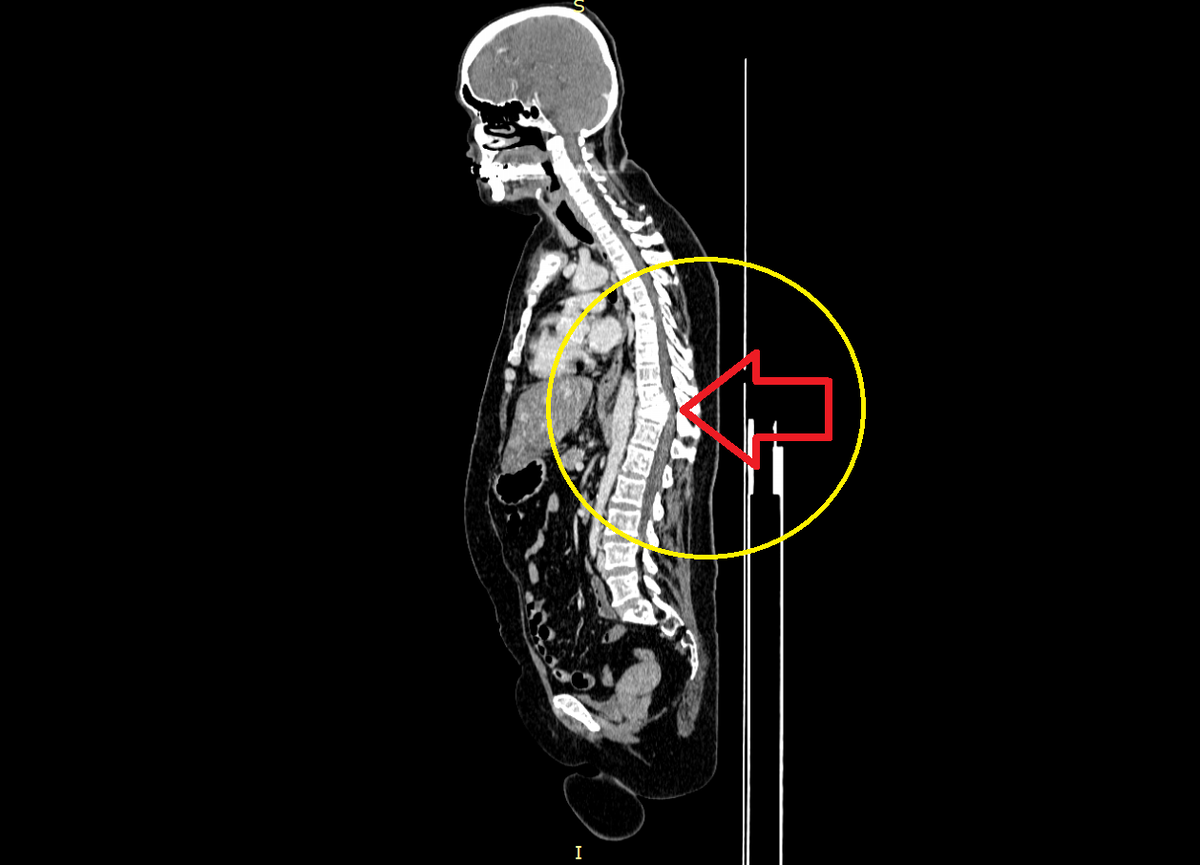

Последние шесть лет пациентка живет с обширным метастатическим поражением костей, в том числе позвоночника. Первое о чем я подумал, было сдавление спинного мозга в области патологического перелома грудных позвонков. Я взял диск, чтобы открыть его и убедиться в истинности моего предположения.

Вот что я увидел:

Стрелка указывает на сдавленный спинной мозг в области перелома позвонков

Конечно, наиболее опасным с точки зрения качества жизни является метастатическое поражение позвоночника. Растущий метастатический очаг разрушает позвонок, из-за чего под воздействием силы тяжести и без каких-либо серьезных травм и физических нагрузок происходит постепенное или резкое снижение высоты позвонка - патологический компрессионный перелом. При определенных обстоятельствах компрессионный перелом позвонка (или нескольких позвонков) приводит к сужению спинномозгового канала и сдавлению спинного мозга — именно это и произошло с пациенткой в описанном мной случае. В зависимости от высоты и степени сдавления спинного мозга, у пациента могут появиться жалобы на слабость в руках и ногах, либо только в ногах. При значительном сужении спинномозгового канала пациент может полностью потерять возможность ходить, также может быть утрачен контроль над функцией тазовых органов. И в ситуации, когда отсутствуют какие-либо другие проявления болезни кроме костных метастазов, пациент рискует на протяжении длительного времени остаться прикованным к постели.